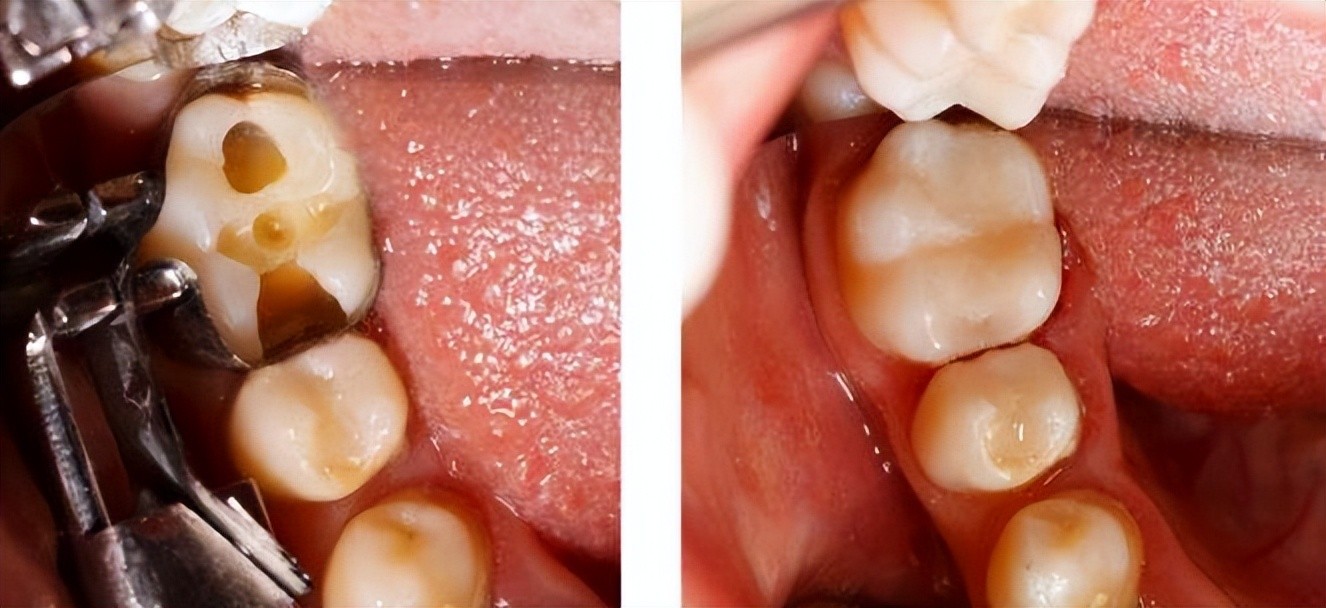

一般情况下,牙齿龋坏不严重的话,只需要进行去腐后使用树脂/玻璃离子/嵌体等材料进行修补即可;如果龋坏严重伤及牙神经,那么就要进行根管治疗,这时候价钱一般比普通不要要高出5、6倍。